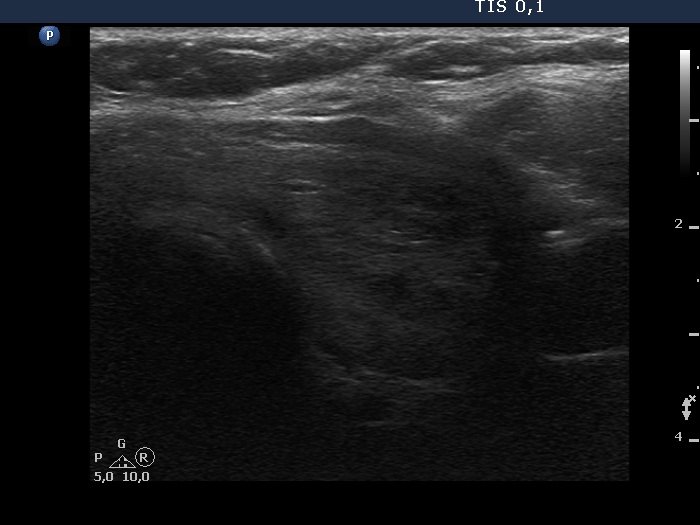

TIRADS - case 1147

Follow-up examination six years after the first visit (ultrasonographic picture 6)

Lower part of the left lobe, transverse scan.